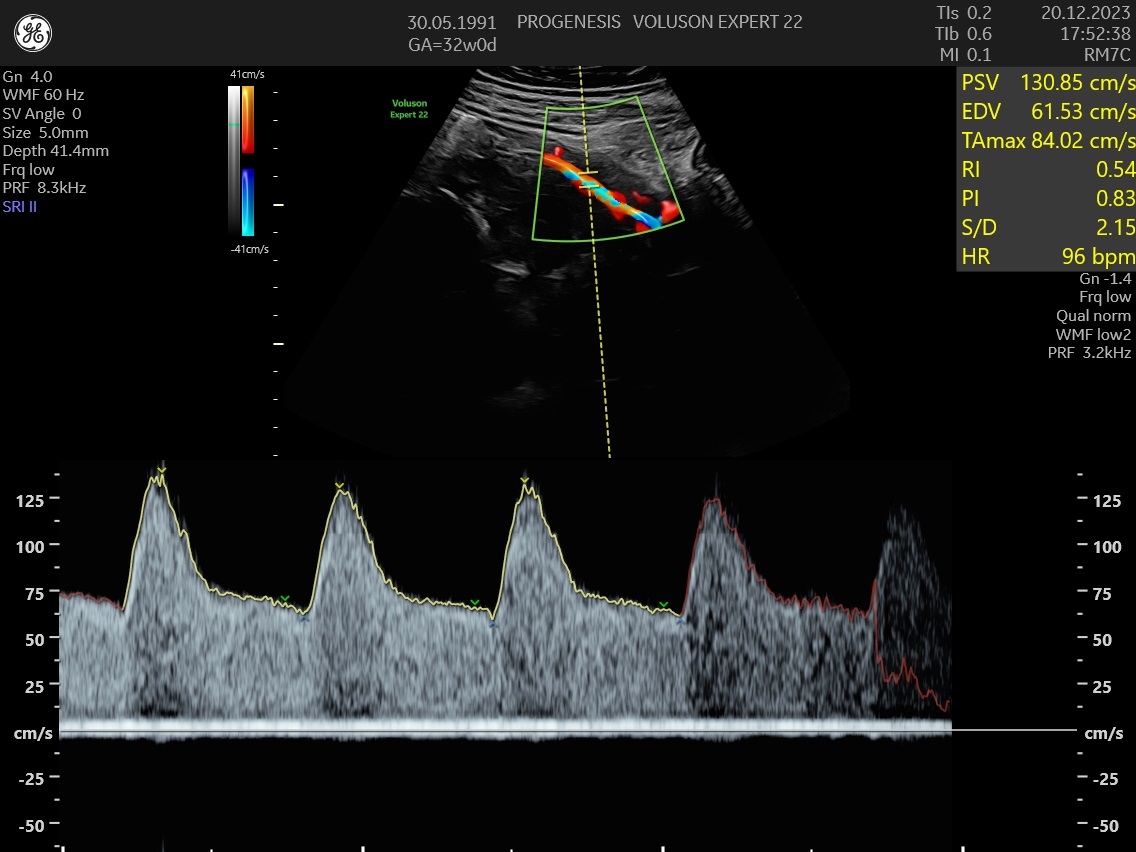

3D/4D LIVE Υπερηχογράφημα

Το 3D/4D LIVE είναι μια νέα τεχνολογία υπερήχων που δημιουργεί εικόνες του εμβρύου σε τρισδιάστατο ή τετραδιάστατο χώρο. Οι εικόνες αυτές είναι πιο ρεαλιστικές από τις παραδοσιακές εικόνες υπερήχων και δίνουν στους γονείς μια πιο ολοκληρωμένη εικόνα του μωρού τους.